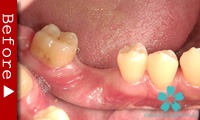

歯を一本だけ失った場合

“失われた1本の歯根の代理品”としてインプラントを1本だけ使って失った歯の部分を修復する方法は、最も洗練された治療方法であり、審美的にも満足のいく結果が得られます。

1本のインプラントによってあたかも自分の天然歯のように自然に感じられます。顎骨の”萎縮”の心配もなく、本来の骨量を維持できます。

ブリッジを入れる時のように、健康な隣の歯を削る必要がありません。